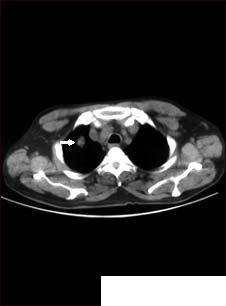

Hemoptizia (expectoratia cu sange)